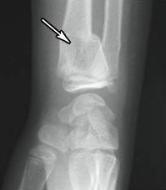

potts fracture